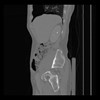

36 CUERPO,CE,Sagittal,3.000,CUERPO,Sagittal,